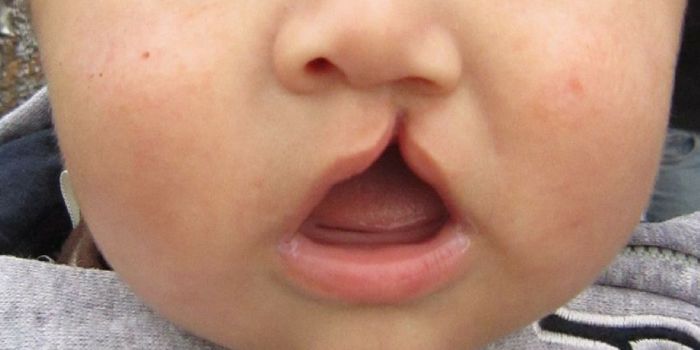

SEP 19, 2017Clinical & Molecular DXResults from a new study suggest that cleft palate, one of the most common birth defects in children, could be reversed ...